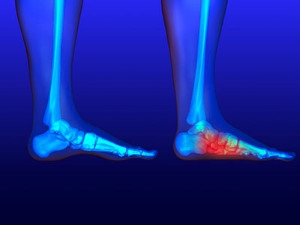

A dislocated toe occurs when the bones in the toe become misaligned, often leading to significant discomfort and mobility issues. Common symptoms include intense pain at the site of the injury, noticeable swelling, and bruising. The affected toe may appear deformed or out of place, and there may be difficulty moving it or walking without pain. Several factors contribute to dislocated toes, with sports injuries being a leading cause. Activities involving running, jumping, or sudden changes in direction can put excessive stress on the toe joints. Also, accidents such as stubbing the toe or dropping a heavy object on it can lead to dislocation. If you have sustained an injury that may have dislocated your toe, it is suggested that you promptly contact a podiatrist who can provide an accurate diagnosis and treatment.

Most severe toe pain is caused due to a sports injury, trauma from dropping something heavy on the toe, or bumping into something rigid. Other problems can develop over time for various reasons.

Toe pain can be caused by one or more ailments. The most common include:

- Trauma

- Sports injury

- Sprains

- Fractures (broken bones)

- Dislocations

In many cases the cause of toe pain is obvious, but in others, a podiatrist may want to use more advanced methods to determine the problem. These can range from simple visual inspections and sensation tests to X-rays and MRI scans. Prior medical history, family medical history, and any recent physical traumatic events will all be taken into consideration for a proper diagnosis.

Treatments for toe pain and injuries vary and may include shoe inserts, padding, taping, medicines, injections, and in some cases, surgery. If you believe that you have broken a toe, please see a podiatrist as soon as possible.

What to Know About a Broken Toe

The forefoot is composed of five metatarsal bones and fourteen phalanges. Each toe has three bones, except for the big toe which only has two. Our toes play an essential role to the walking process, which is why a broken toe could seriously disrupt one’s ability to move around. Toe fractures are common and can be very painful. Fortunately, these injuries rarely require surgery and usually heal with rest and a change in activity.

Broken toes typically result from a traumatic event such as falling, stubbing the toe, or dropping something on the toe. Traumatic toe fractures may be categorized as either minor or severe fractures. At times, one may hear a “pop” or “crack” sound when the bone breaks. Common symptoms of a traumatic toe fracture include pain, throbbing, bruising, swelling, and redness.

Another type of fracture is usually of the metatarsal, which is behind the toes and these bones can have stress fractures. These injuries usually appear in the form of small hairline breaks on the bone. Stress fractures develop after repetitive activity.

If you suspect that you have a broken toe, you should make an appointment with Dr. DiNucci. He will likely diagnose you by performing a physical exam and an X-ray. Treatment for a broken toe may include the R.I.C.E. method, buddy taping, surgery, or antibiotics. The R.I.C.E. method (Rest, Ice, Compression, and Elevation) is a common treatment method for many injuries because it decreases pain. Buddy tapping involves wrapping the injured toe next to an adjacent toe to keep it supported and protected. These two methods have proven to be effective in the healing process for toe fractures. The estimated healing time for a broken toe is approximately four to six weeks. If the injury becomes infected or requires surgery, the estimated healing time may take eight weeks or more.